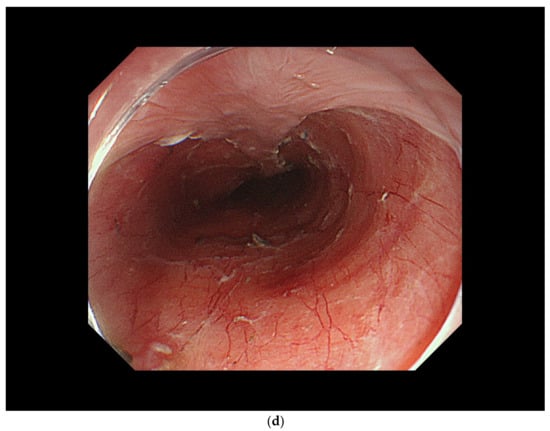

4.3. ER Procedure

5. Curability Assessment